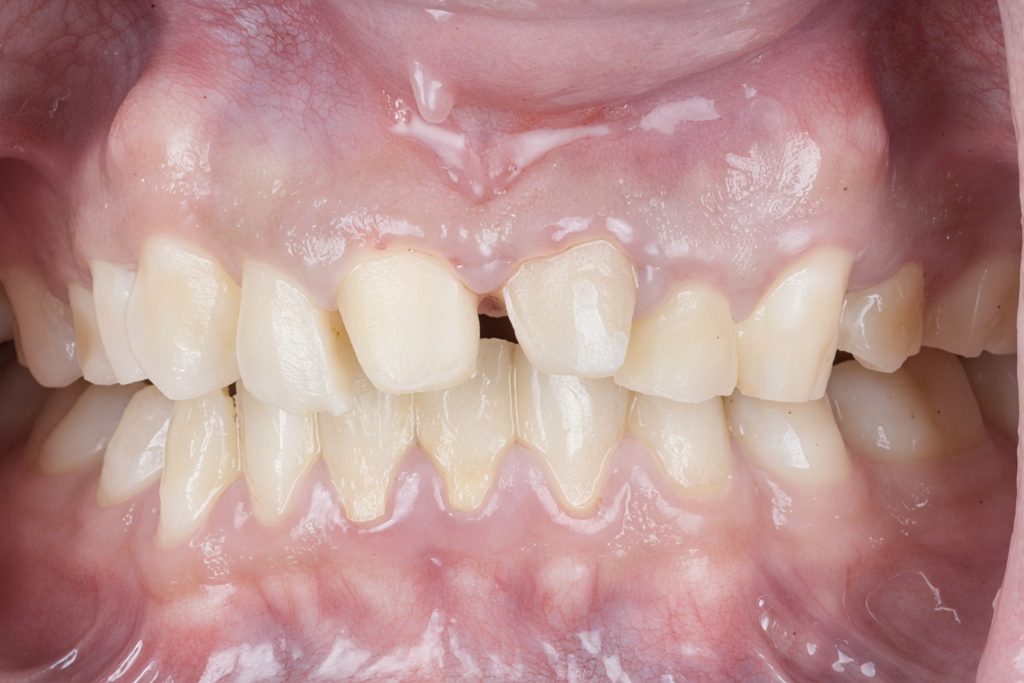

Pre-Operative Assessment

Clinical findings included:

- Irregular lengths and fractured enamel edges

- Poor axial inclination of centrals

- Previous composite restorations discolored and debonded

- Mild gingival inflammation

- Pulpal involvement confirmed radiographically

Primary goals: Restore function, protect remaining tooth structure, correct smile proportions, and achieve long-term stability.